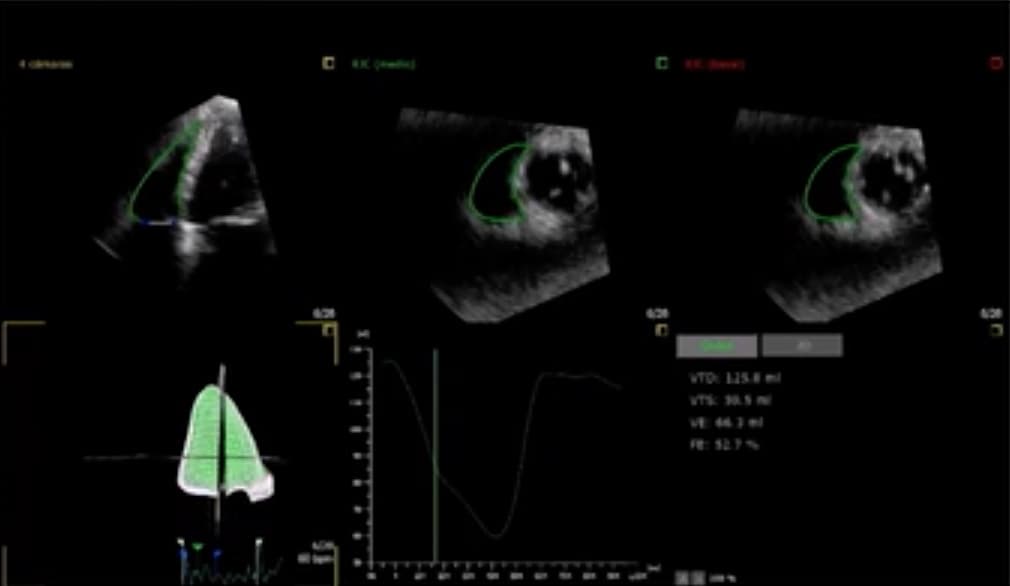

La plateforme Radcliffe Cardiology a récemment mis en ligne un webinaire dédié à l’insuffisance tricuspidienne. Les experts qui l’animent évoquent les dernières recommandations européennes relatives au diagnostic de régurgitation tricuspidienne ainsi que les procédures thérapeutiques diverses à mettre en place selon le profil du patient.